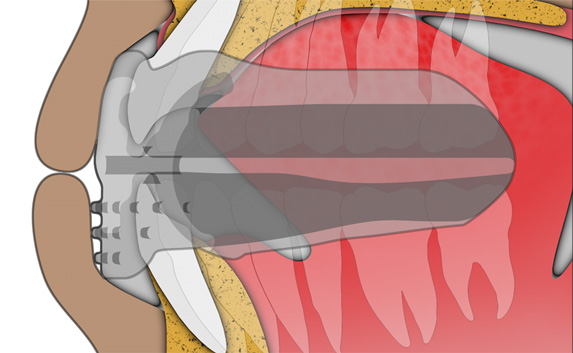

The B1 focuses on establishing nasal breathing and myofunctional habit correction for patients who are using braces. It is soft and flexible, giving the best compliance, while being adaptive to any arch form and malocclusion. It has small breathing holes to establish continuous nasal breathing and myofunctional features to promote correct habits. It also features braces channels to accommodate brackets and wires. The B1 is ideal for initial levelling and alignment with fixed orthodontics but can also be used throughout the entire orthodontic treatment plan.